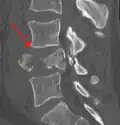

Diagnosis is by medical imaging.

A burst fracture of L4 as seen on CT -